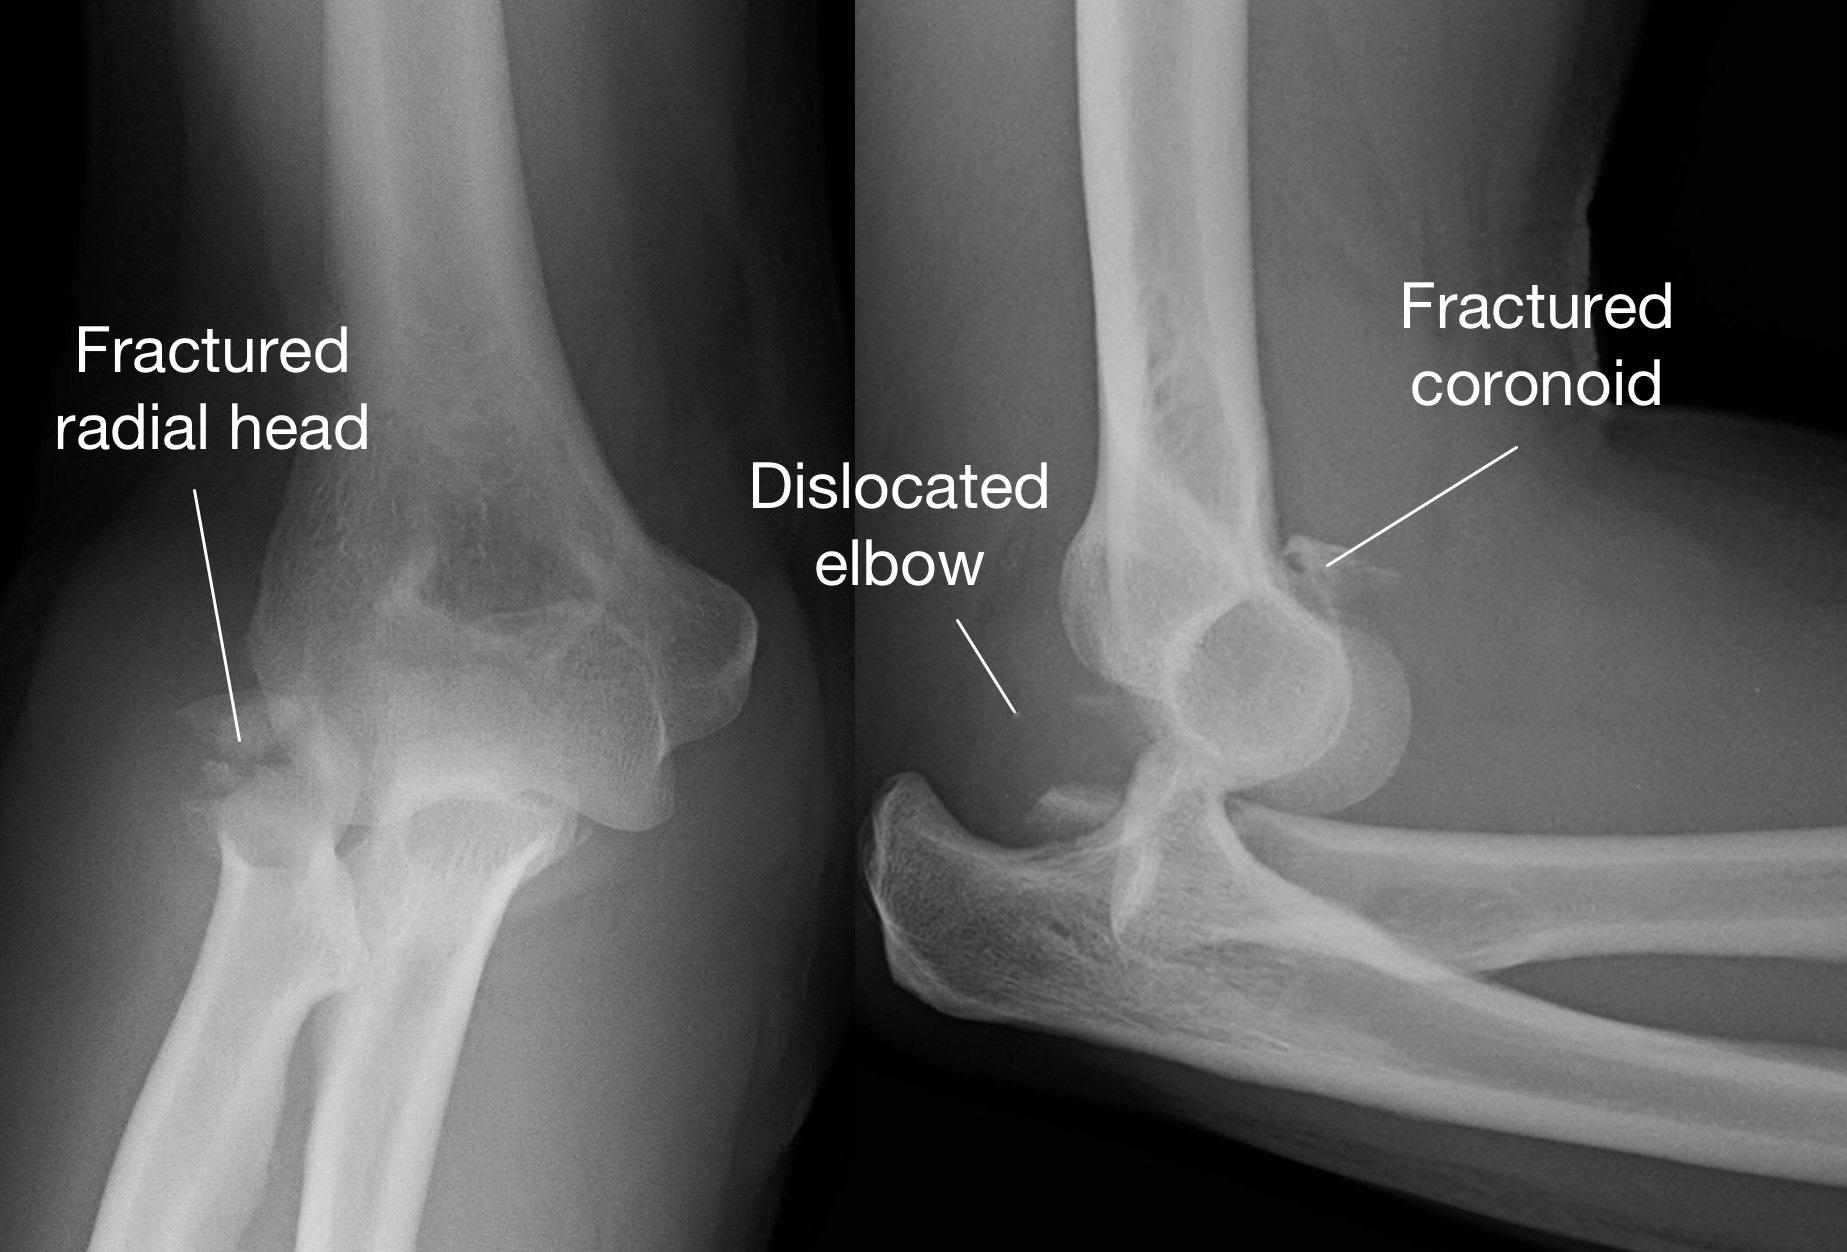

小風原本在放學後要與同學去慶祝生日,不料卻在途中發生車禍造成左手肘整個彎曲變形痛不欲生。送急症室發現是左手肘的粉碎性骨折合併脫臼,緊急實施手肘關節的復位手術後並安排電腦斷層檢查。沒想到不只手肘的橈骨和尺骨是粉碎性骨折,手肘韌帶還斷了3條,這是骨科醫生最害怕的手肘脫臼恐怖三聯症(Terrible Triad Injury of Elbow)。

大里仁愛醫院骨科部長黃贊文醫生表示,手肘脫臼恐怖三聯症大部分發生在年輕人和中年人,主要是因為車禍或高處墜落等高能量撞擊所導致。手肘脫臼恐怖三聯症是相當嚴重的情況,因為不只是手肘關節發生脫臼,關節旁邊的橈骨頭和尺骨冠狀突常是粉碎性骨折。而最令骨科醫師感到棘手的是手肘關節的韌帶往往也斷裂,因此不只是將脫臼的手肘關節復位和固定好骨折,若不修補好韌帶,手肘關節依然不穩定而失去功能。